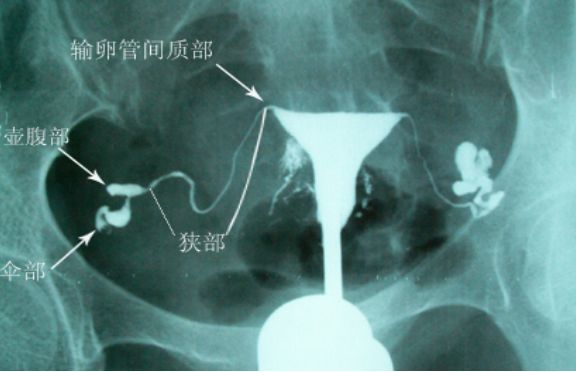

经X线的输卵管介入复通术是在数字X光机下医生通过电视屏直视下采用同轴导管系统,经阴道、宫颈、子宫、子宫角向输卵管插入输卵管导管,进行输卵管选择性造影,再依据输卵管的具体堵塞部位和具体情况经输卵管导管向输卵管插入输卵管导丝,通过导管丝对于堵塞的输卵管进行复通分离的治疗过程。

主要用于输卵管不通,特别是输卵管间质部及峡部粘连阻塞等。

造影视:双侧输卵管近段狭窄,右侧伞端通而不畅,左侧输卵管管壁不规则,通而不畅。